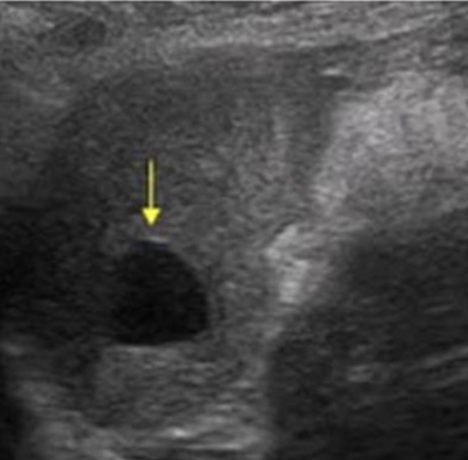

Simple Renal Cyst → common lesion of kidney, fluid-filled sac (benign, Bozniak 1)

2D US: anechoic, well-defined smooth, thin wall, round or ovoid, posterior enhancement

color doppler: avascular

DDX: complex cyst